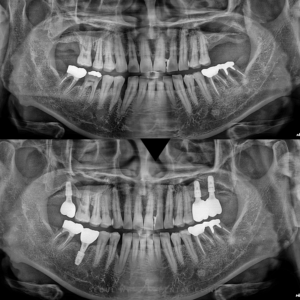

오래된 앞니 보철물과 잇몸의 경계 부위가 넓어져서 일상생활의 불편함을 느끼시고, 경계 부위의 깨진 치아가 걱정되어 내원하신 분의 치은성형술과 심미보철치료 사례를 소개해 드리겠습니다.

대교동심미보철 서울화이트S치과에 처음 내원하셨을 때 모습입니다. 오랜 기간 관리를 하지 못하셔서 치은의 경계 부위가 많이 노.출되었고, 굴곡 파절이 있는 곳도 있기 때문에 단순히 다시 잇몸라인에 맞춰서 제작하면 보기 좋지 않을 뿐만 아니라 예후도 좋지 않을 것으로 판단하였습니다.

또 하고 계신 보철물의 색상과 투명도가 주변 치아와 맞지 않은 모습이셔서 많이 신경 쓰이셨을 것으로 보였는데요. 서울화이트S치과는 잇몸의 형태를 생리적으로 재형성시키는 외과적인 시.술인 ‘치은성형술’로 건강하게 보이는 잇몸라인을 만들어드리고, 치질을 단단하게 보강하여 안정적이고 심미적인 보철물을 제작해 드리는 것으로 치료 계획을 수립하였습니다.

잇몸의 충분한 회복을 확인하고, 최종 보철물이 제작된 모습입니다! 잇몸 경계 부위가 잘 맞게 제작된 것을 볼 수 있는데요. 환.자분과 충분히 의논하여 결정한 자연스러운 치아 색상과 형태로 마무리되었습니다. 어금니 부분까지 제작해 드리고, 치아에 무리가 가지 않도록 교합조정까지 세심하게 해드렸어요:)